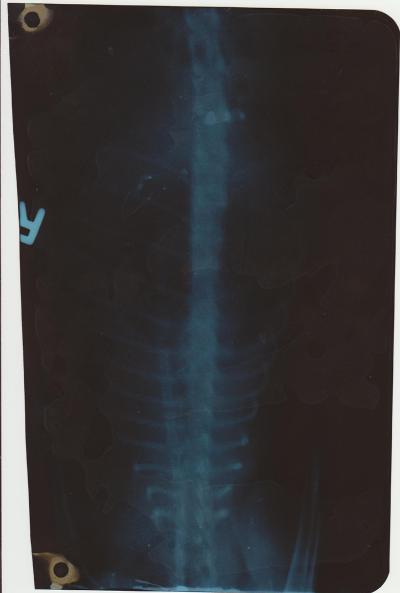

Легкие рентген 80% мутные

после лечения первого 70%

далее возврат к 80%

После последнего курса не делал, но судя по дыханию 65- 75%

Снимок неинформативен. Нельзя по такому снимку говорить об отёке или не отёке лёгких, и тем более, о его причине и лечении.

Проблема в лёгких, наверняка есть, судя по симптомам, но это может быть как отёк, так и свободная жидкость, так и новообразование. Лечение принципиально разное.

Рентген нужно переделать, в боковой проекции.